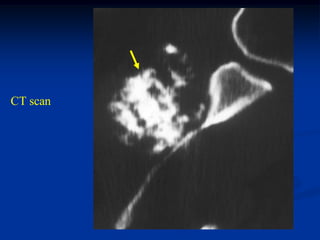

Case #551

62 year male

enchondroma

proximal humerus

Coronal T-1 MRI

CT scan